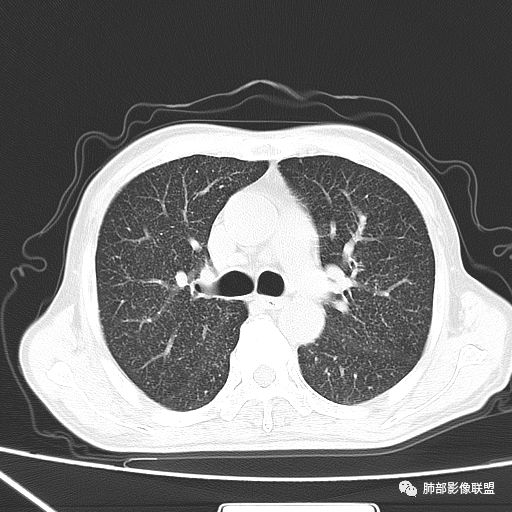

2019-10-20复查CT如下:

两肺弥漫性粟粒样结节伴左上肺小结节,呈三均匀分布,有结核的临床表现,支持血性播散性肺结核。

大小、分布均匀,边缘清楚

细小结节,弥漫,撒米粒样——血道来源

血道来源的病灶,均匀、细微,而且部分有分支状,都符合粟粒型肺结核

急性血行播散型肺结核  两肺广泛分布粟粒大小的结节状密度增高影,具有大小均匀、分布均匀、密度均匀的典型“三均匀”特征,注意急性血播病灶非常小,一般粟粒影直径1~2mm。

病灶密集者出现肺外围血管影不清或减少。

发热初期肺部可缺乏典型影像学改变,1到2周后出现的广泛粟粒结节对诊断具有高度提示作用!